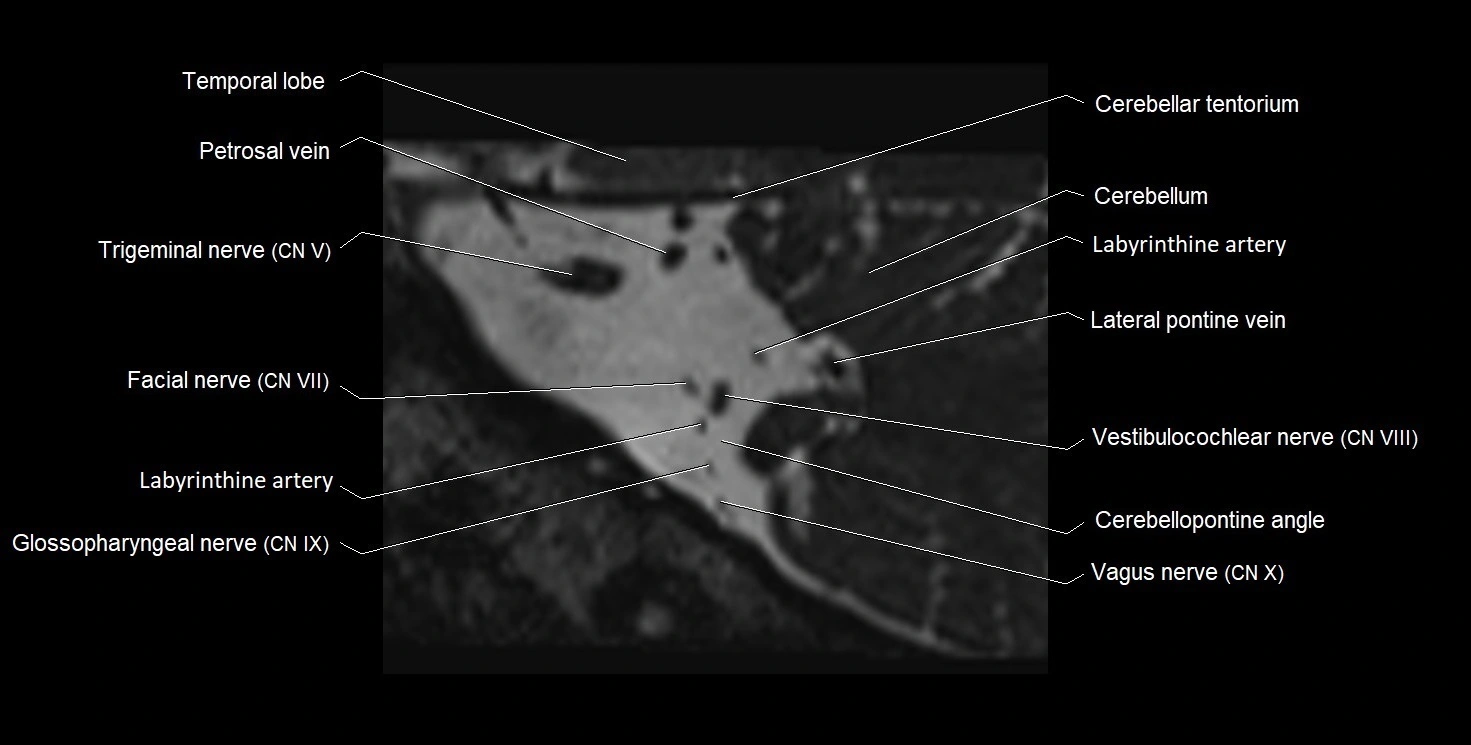

MRI images

image